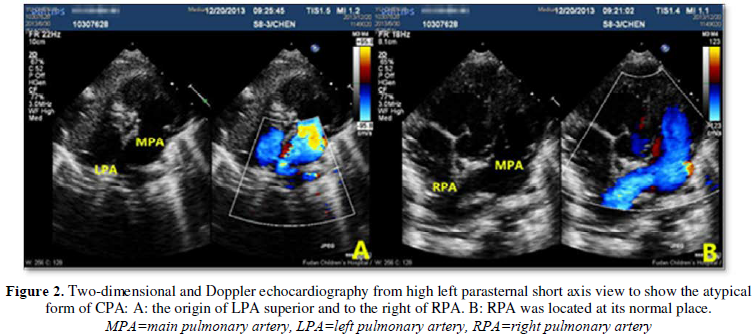

The direct sign of CPA was displayed at the

high left parasternal short-axis view and the suprasternal fossa view, while

the typical bifurcation disappeared in the routine left parasternal view. For

the typical form, moving the probe up 1 or 2 intercostals in the high

parasternal view and sweeping from superior to inferior to show the left

pulmonary artery was located in the right to the pulmonary artery and above the

right pulmonary artery, and the right pulmonary artery was located in the left

to the pulmonary artery and below the left pulmonary artery (Figure 1). For atypical form, in the high left

parasternal view, the main pulmonary artery continues to the right or left

pulmonary directly (Figure 2), then

the left pulmonary artery was located just above the right pulmonary artery or

the right pulmonary artery was located below the left pulmonary artery. There

were no other indirect echocardiographic signs of the single CPA.